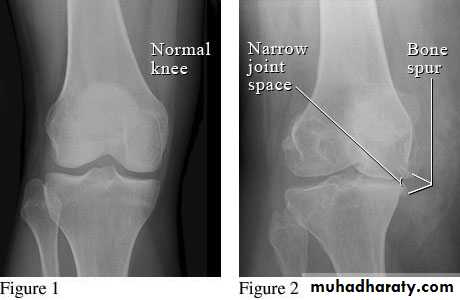

Plain X-ray of the affected joint (diagnostic features, severity of structural damage)Non-weight bearing postero-anterior views of the pelvis are adequate for assessing hip OA.

Patients with suspected knee OA should have standing antero-posterior radiographs taken to assess tibio-femoral cartilage loss, and a flexed skyline view to assess patello-femoral involvement.

Spine OA can often be diagnosed on plain X-ray, which typically shows evidence of disc space narrowing and osteophytes.

Characterised by:Focal loss of articular cartilage

Subchondral osteosclerosisOsteophyte formation at the joint margin

Fibrocartilage is produced at the joint margin, which undergoes ossification to form osteophytes.Bone remodelling and cartilage thinning slowly alter the shape of the OA joint, increasing its surface area.